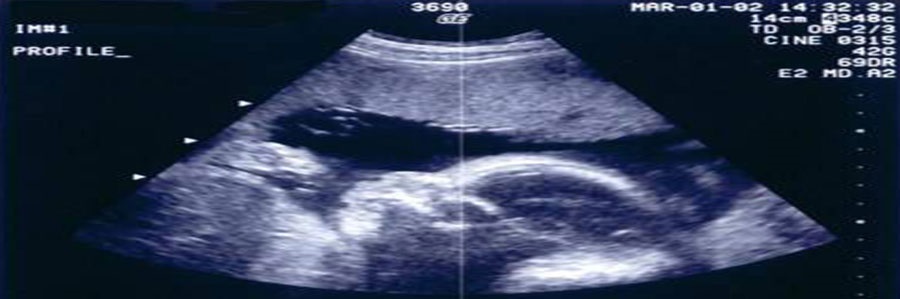

انجام سونوگرافی در طی دوران بارداری به عنوان روشی برای بررسی سلامت جنین (تعیین سن جنین، تشخیص ناهنجاری ها ومشکلات کروموزومی و...) مورد استفاده قرار می گیرد.

سونوگرافی سوم: بهتر است بعد از هفته 18 یک سونوگرافی برای تشخیص ناهنجاری های جنین انجام شود. چون تقریبا تمام اعضای جنین در این زمان شکل گرفته است . در هفته های18 تا 22 بارداری دست و پا، تعداد انگشتان، صورت، وضع لب ها، گوش، چشم، دیافراگم، ستون فقرات، کلیه ها، مثانه و معده پر از مایع و چهار حفره ای بودن قلب جنین بررسی می شود. به این سونوگرافی آنومالی اسکن میگوییم، واز انجا که در کشور ما، بعد از هفته 19 حاملگی، حتی در صورت وجود ناهنجاری اجازه ختم بارداری داده نمیشود، بهتراست این سونوگرافی در هفته ی18 و تا قبل از پایان 19هفتگی انجام شود ، تا در صورت نیاز برای اجازه قانونی جهت ختم بارداری اقدام کنیم.